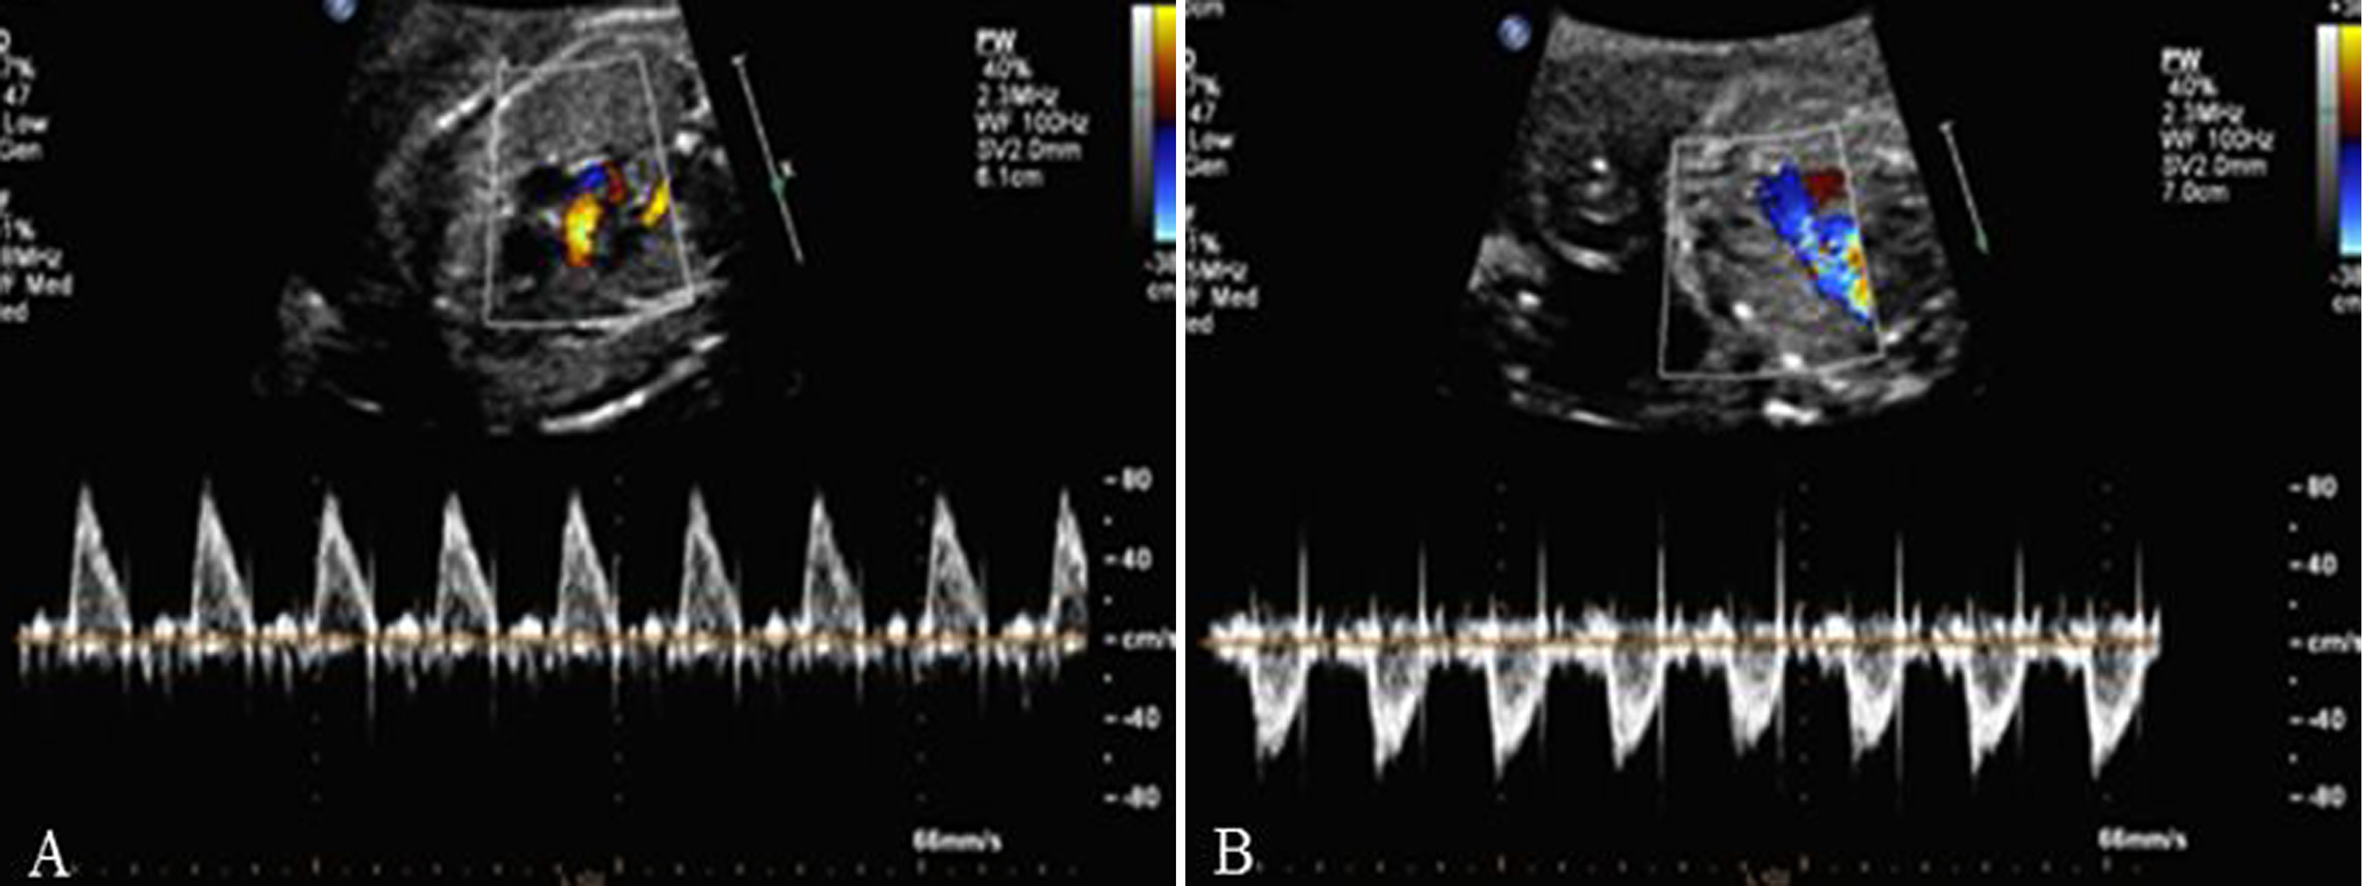

CDFI检查胎儿二尖瓣口(MVO)显示为稍细的红色血流,三尖瓣口(TVO)的红色血流较MVO稍粗;TVO的血流速度较MVO快。在瓣口远端取样,可以获得MVO和TVO的血流频谱,舒张期显示E峰和A峰。E峰由心室舒张的快速充盈血流形成,A峰由缓慢充盈期心房收缩、血流加速而形成,双峰特点在MVO显示的更为明显(图1)。瓣口血流速度随着孕龄的增加而增加,但38孕周后血流速度有所下降。

图1 MVO(A)和TVO(B)流速曲线,E峰<A峰

胎儿心室充盈的最大血流速度出现在心房射血期,由此导致MVO和TVO显示E峰小于A峰,提示心房收缩在胎儿心室充盈中起了重要作用;随着孕周增加E/A比例增大,说明心室舒张能力逐渐增加。出生24h后E/A即可升至1.17。TVO流速>MVO流速,显示胎儿循环为右心室(RV)优势;这种右室优势在早孕期即开始,直到在孕晚期才逐渐转为左室优势。